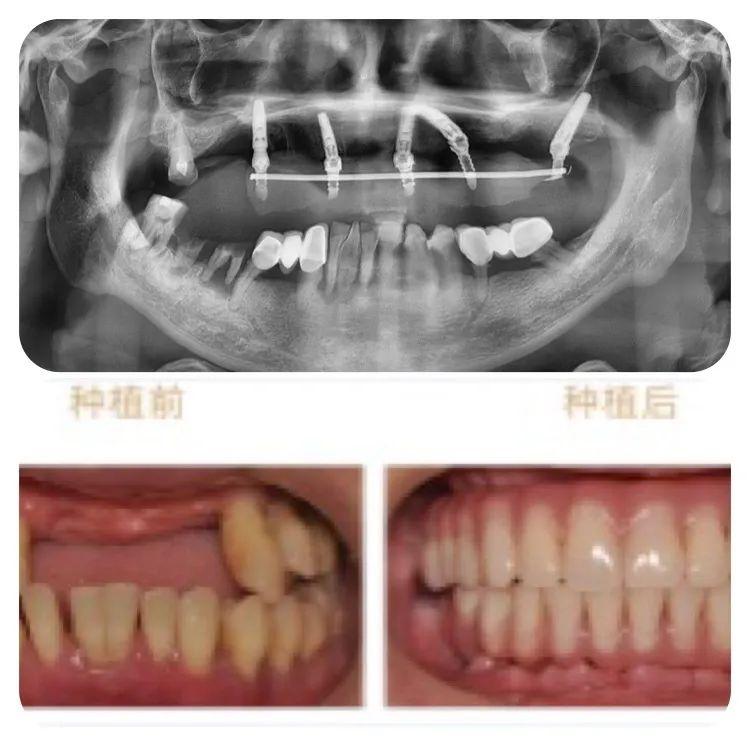

此次成功種牙的78歲高齡的老人,不但同時(shí)患有高血壓、心臟病及糖尿病,口腔條件也不容樂觀:因外傷引起牙缺失2年,有較嚴(yán)重的牙周炎,是典型的高齡疑難種牙案例。

針對老人的口腔條件,重慶泰康拜博口腔VIP種植工作室通過3D數(shù)字化種植設(shè)計(jì)系統(tǒng)為他個(gè)性化計(jì)了帶1顆穿翼板種植的負(fù)重種植牙方案,即拔即種,全口牙在1天之內(nèi)完成了種牙、戴冠全過程,手術(shù)完成后帶上臨時(shí)牙冠,牙齒就已經(jīng)可以正常使用。

術(shù)后1周復(fù)查,通過口腔CT檢查,可以看見老人的種植牙、穩(wěn)固。老人自己也描述,他在種牙的時(shí)候感覺輕松快速,幾乎沒有痛感,打個(gè)盹的功夫,牙齒就種好了。